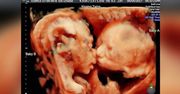

USG transwaginalne, inaczej badanie ultrasonograficzne przezpochwowe jest niezwykle użytecznym i powszechnie stosowanym badaniem w ginekologii i położnictwie. Jest prostą w wykonaniu, nieinwazyjną i bezbolesną metodą diagnostyczną, która przy wykorzystaniu zjawiska odbicia, rozpraszania i rozchodzenia się fal ultradźwiękowych o częstotliwości w zakresie 2-50MHz pozwala na uzyskanie obrazów przekroju badanych narządów. Obrazy te są dobrej jakości i dzięki temu pozwalają na prawidłową ocenę stanu narządów wewnętrznych, wykrywanie różnego rodzaju nieprawidłowości, a nawet bardziej precyzyjną diagnostykę pod kontrolą obrazu USG. Z tego względu, a także ze względu na bezpieczeństwo tej metody dla zdrowia pacjenta, znalazła ona szerokie zastosowanie we wszystkich dziedzinach medycyny. USG przezpochwowe jest stosowane do oceny stanu żeńskich narządów rozrodczych najczęściej z racji tego, że badanie USG przez powłoki brzuszne jest w tym przypadku utrudnione przez obecność upowietrznionych pętli jelitowych. Badanie to powinno być rutynowo stosowanym uzupełnieniem badania ginekologicznego, gdyż w wielu przypadkach pozwala na wykrycie takich nieprawidłowości, które są niemożliwe do rozpoznania w badaniu ręcznym.